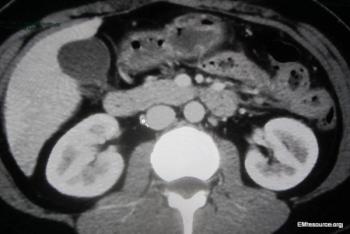

The 26-year-old patient has a history of type 1 diabetes; no other prior medical or surgical history. Antiemetics have failed. Can you Dx?

The patient has had 10 episodes of bleeding in the past 24 hours. Can you find clues to the underlying problem in the history and on the CT scan?